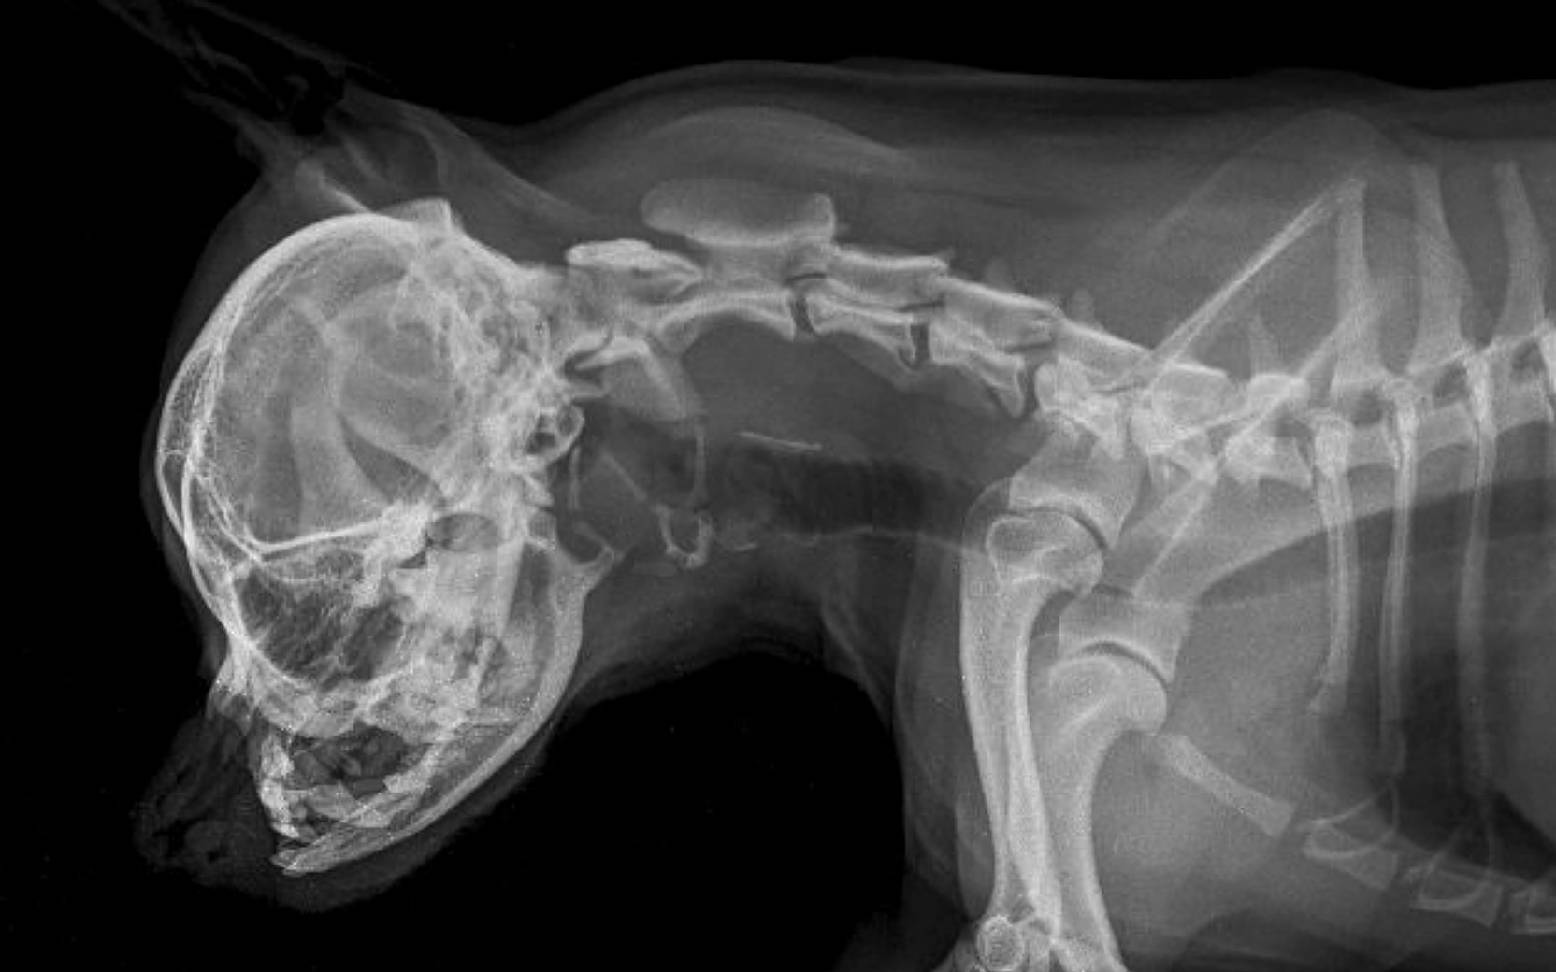

The word brachycephaly comes from Greek and means short-headed or round-headed. It describes the hereditary shorter and wider skull shape of some dog and cat breeds, which is reminiscent of the "childhood pattern" of young animals. The health consequences of this shortened facial skull are far-reaching and are referred to as brachycephalic syndrome.

Brachycephalic syndrome is caused by centuries of selective breeding to inhibit the growth of the facial skull. In relation to the smaller facial skull, the size of the tissues inside has not decreased during development. This leads to narrowing, malformations, and thickening in the nose and larynx. Since dogs, like cats, are obligate nasal breathers (=they must breathe through their nose), this explains why these changes cause such a wide range of problems for these animals. Breeds affected include French and English bulldogs, Pugs, Boston terriers, Cavalier King Charles spaniels, Pekingese, Lhasa Apsos, Pinschers, and Persian cats.

The nostrils of affected animals are too narrow and the nasal conchae in the nose are too large for the small skull. The animals have to exert significantly more effort when inhaling in order to overcome this resistance in the airways. This creates negative pressure in the larynx and trachea, which can lead to further narrowing or even collapse of these structures (see article on tracheal collapse). The consequences are sniffling, snoring, grunting, or wheezing noises that can be heard with every breath. These additional breathing noises are neither normal nor typical of the breed and do not reflect well-being, as is often mistakenly assumed by owners.

Additional breathing difficulties, including severe respiratory distress, can result from a palate that is too long, thickened, or flaccid. During inhalation, this palate covers the opening of the larynx, partially or completely closing it. Furthermore, a shortened pharynx, a relatively large tongue, laryngeal collapse, which is particularly common in pugs due to unstable laryngeal cartilage, or excessively developed mucosal folds can lead to worsening breathing difficulties.

The consequences of permanent respiratory distress and the resulting oxygen deficiency are cardiac arrhythmia with subsequent heart failure, which can ultimately lead to death. Further complications can include difficult births, brain tumors, hydrocephalus, poor dental function due to a shortened upper jaw and underbite, proptosis, corneal injuries, and obstruction of the flow of cerebrospinal fluid.

After a thorough general examination and your detailed preliminary report, your veterinarian will often be able to make a preliminary diagnosis. The throat and larynx will then be examined more closely. As this can almost only be done under sedation or anesthesia, this examination is usually combined with surgery. Further X-ray or CT scans can be used to determine the exact extent of the changes.